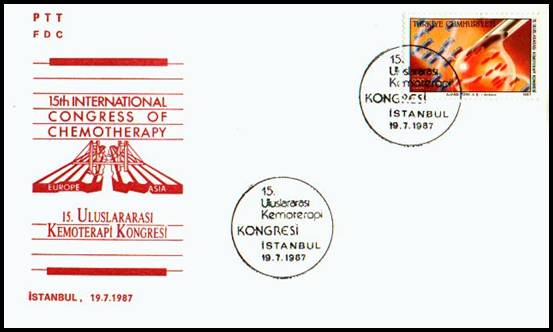

MEDICAL

CONGRESSES